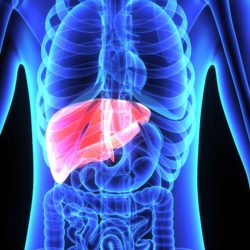

Amiodarone and other prescription and over-the-counter drugs as well as herbal and vitamin supplements can cause drug-induced liver disease. When the liver functions properly and at its full capacity, it accomplishes multiple tasks.

Among these tasks, according to Medicine Net, are the production and secretion of bile which breaks down dietary fats, the purification of blood by changing damaging chemicals into anatomically harmless ones, the removal of harmful chemicals—usually by this same process—and setting them up for secretion through the renal system or solid waste, and the creation of proteins that allow for proper clotting of the blood and other body processes.

Although there are many ways in which liver toxicity from drugs can show themselves, Amiodarone has been specifically linked to cholestasis. Cholestasis is a health situation in which the secretion and flow of bile has been compromised. Bilirubin and bile acids build up in the body and frequently are experienced as jaundice and itching. Jaundice is noted as a generalized yellowing of the skin.